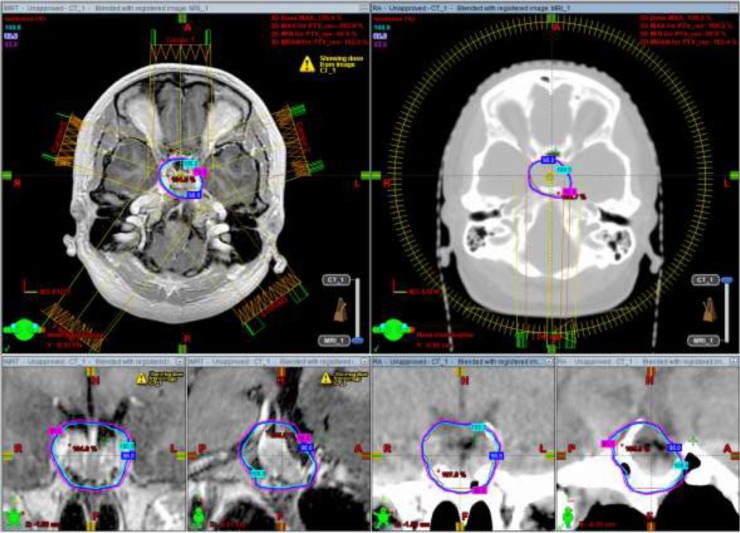

Fig. 2.

Isodose curves of D100% (cyan), D98% (blue) and D95% (magenta) with IMRT (left) and VMAT (right) with axial, coronal and sagittal views of MRI and CT, respectively. Abbreviations: IMRT, modulated intensity radiotherapy; VMAT, volumetric modulated arc therapy; MRI, magnetic resonance imaging; CT, computed tomography. (For interpretation of the references to colour in this figure legend, the reader is referred to the web version of this article).